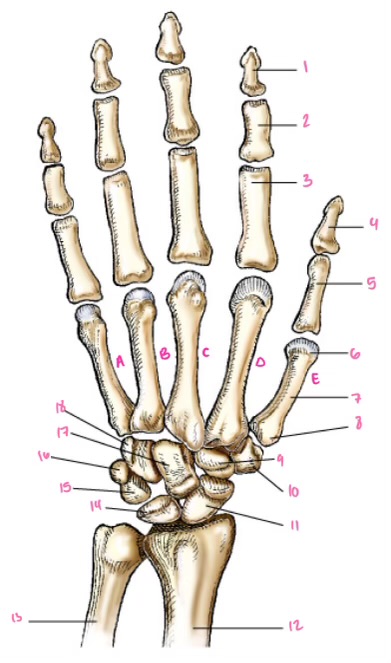

1

1

2

2

3

3

4

9

5

10

6

11

7

14

8

15

9

16

10

17

11

18

1

13

2

14

3

15

4

16

5

17

6

18

7

19

8

20

9

7

22

8

23

9

24

10

25

11

26

13

27

14

28

15

29

16

30

17